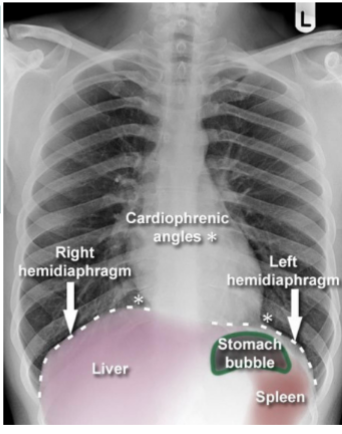

Label this CXR (10 things)

1) trachea 2) hilum- should have R and L 3) lungs 4) diaphragm 5) heart 6) aortic knuckle 7) ribs 8) scapulae 9) breasts 10) bowel gas

Identify cardiophrenic angle, R + L hemidiaphragms, stomach bubble, liver, spleen

yes